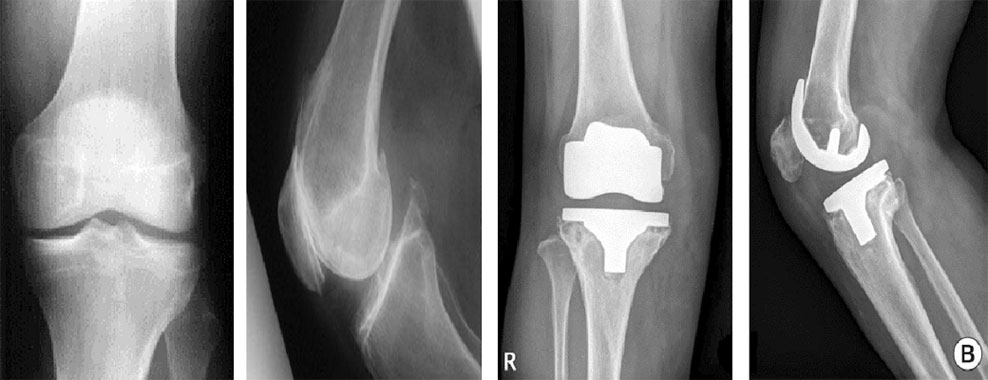

Chronic knee pain can make even simple tasks—walking, climbing stairs, sitting, or standing—extremely difficult. At HappyKnees, we offer advanced Primary Knee Arthroplasty in Malad, performed by leading orthopedic specialist Dr. Akash Saraogi. This procedure, also known as Primary Knee Replacement, involves replacing the damaged knee joint with high-quality artificial implants to restore smooth, pain-free movement.

Primary Knee Arthroplasty is ideal for patients suffering from severe arthritis, cartilage loss, joint deformity, old injuries, or progressive knee degeneration. With minimally invasive techniques, precision-aligned implants, and faster recovery protocols, HappyKnees ensures patients regain mobility, comfort, and confidence without long-term discomfort or stiffness.

Primary knee arthroplasty is a surgical procedure in which the damaged surfaces of the knee joint are replaced with artificial implants to relieve pain, correct deformity, and restore smooth movement.